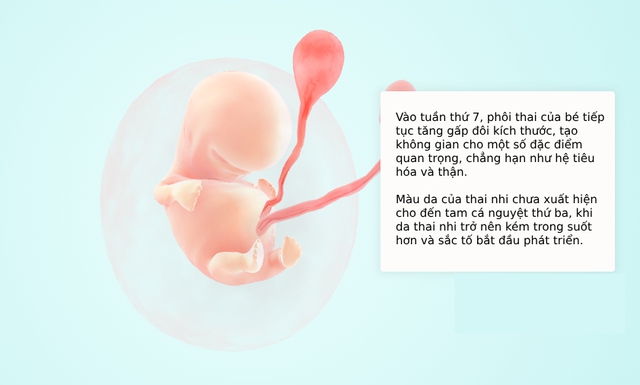

Bước vào tuần thứ 7 của thai kỳ, từ đầu đến chân của phôi thai có kích thước khoảng 10mm, nặng khoảng 0.8 gam và bằng quả nho.

– Bé yêu hiện là một phôi thai, dài khoảng 5-9mm (như hạt đậu), với tim đập đều đặn (110-160 lần/phút) – một khoảnh khắc đầy cảm xúc!

– Túi ối và nhau thai phát triển, cung cấp oxy và dưỡng chất cho bé.

– Đầu, mắt, tai, miệng, và chi sơ khai đang định hình, với cánh tay/chân như chồi nhỏ. Siêu âm có thể cho mẹ thấy túi ối, tim thai, và chi sơ khai. Thật tuyệt vời!